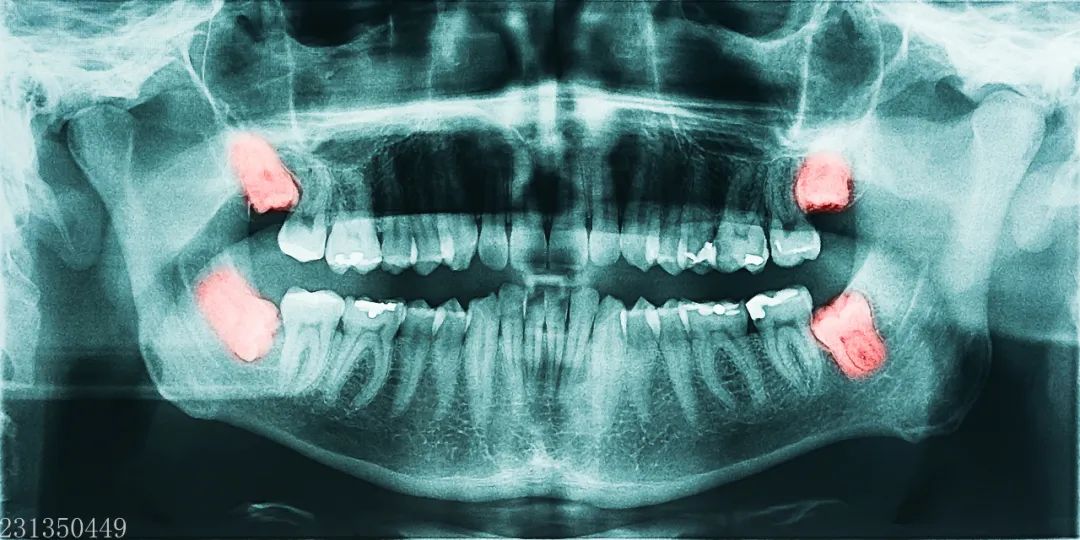

智齿是指人类口腔内牙槽骨上最里面的第三颗磨牙,从正中的门牙往里数刚好是第八颗牙齿。

不管痛不痛,长歪的智齿都要拔!也就是说,尽管暂时没有引起疼痛,那些长歪的智齿,越早拔除越好。发炎的智齿是身体上的一个病灶,会产生很多炎症因子和毒素等有害物质。

炎症因子、毒素等会顺着血流流经身体各个部位,引起局部红肿、呼吸困难,甚至危及脏腑,造成生命威胁。这是因为,长歪的智齿不容易清洁,食物常常会留在智齿周围,不仅容易导致智齿疼痛,还容易导致智齿前方的磨牙变为蛀牙,从而引起更大范围上的牙痛。